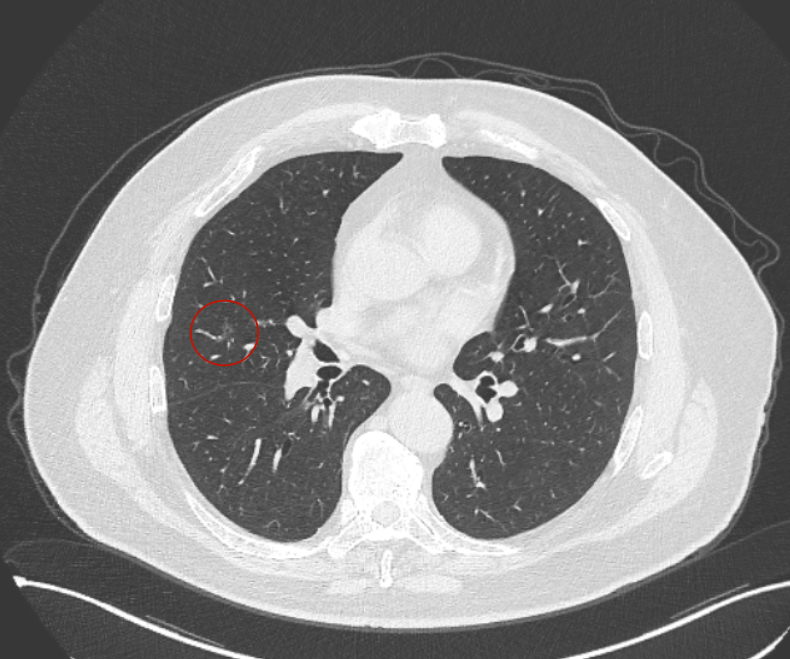

方形的是25年的,红色的主病灶,磨玻璃密度伴少许略偏高点密度,但还说不上典型混合磨玻璃病灶,考虑原位癌或微浸润性腺癌可能性大;蓝色的轮廓与边界欠清,位置靠上叶中央,无法段切或楔切;黄色的多发均淡而纯,分布在两肺。圆形粉色的是主要的两处23年时的样子,对比说不上很明显进展。鉴于若手术得切肺叶,何况两肺他处仍的结节,年纪又74了。我倾向保守点,先6-9个月复查,等进展并风险增加再来考虑怎么办的事。意见供参考!

我的想法是主病灶在右上叶,且多发,而且位置较深,若手术很可能要切且叶,虽考虑是肿瘤范畴的,但由于不管病灶A还是病灶B均仍是磨玻璃密度,没有纵隔窗可见的实性成分,在两肺多发病灶的情况下,适当保守点再随访下,待有进展并风险增高再干预也不至于影响预后。而且根据既往经验,磨玻璃密度的肺癌基本太会短时间内快速进展。

病灶B似乎灶内有少许密度略偏高,但瘤肺边界欠清晰,总体说不上太显著的进展。

当时结友自己还觉得有点实性成分,血管感觉也有增粗。而我觉得整体密度仍是磨玻璃,轻微的变化仍不足以影响临床决策的程度。

病灶没有确切纵隔窗可见的实性成分,但与血管关系较为密切。